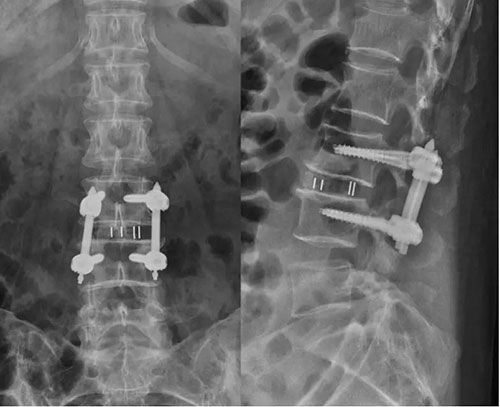

在助手副主任医师李涛、张稳博士辅助下,蒋振松主任医师成功为患者实施椎间孔镜下腰椎融合手术,这也是山东省立医院首例椎间孔镜下腰椎融合手术。手术出血量约50ml,不用放置引流管。患者术后腰痛及下肢疼痛、麻木症状完全缓解,复查X光片显示滑脱完全复位,内固定物位置良好。复查CT和MRI显示侧隐窝狭窄解除,恢复正常椎管容积。患者术后3天CRP、血沉即恢复正常,佩戴腰围下地活动,随即出院。患者及家属对手术效果非常满意。

术后X光